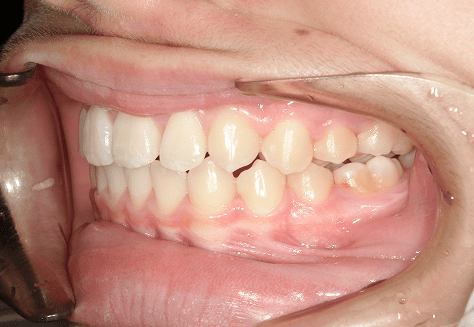

M.U

治療前

治療後

主訴

下の歯が特にガタガタなのが気になる。上の前歯が1本反対になっている。

診断

下顎前突・叢生・反対咬合

年齢/性別

20代/男性

抜歯部位

非抜歯

使用装置

上下インビザライン(PBM使用)

保定装置

ビベラリテーナー

診察料金

5,500円×16回

治療期間

1年7カ月